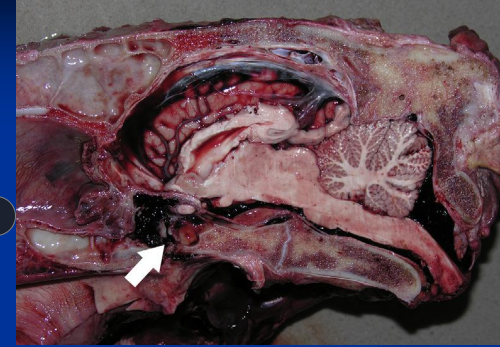

Leukoencephalomalacia: mycotoxin Moldy Corn Poisoning

Et: Fusarium verticilloides (fumonisin B1),

liquefactive necrosis of cerebral hemispheres and liver damage

Cs: rapid progressive signs, ataxia, blindness, seizures, agitation, death

Dt: toxin in feed

Tx: Euthanasia